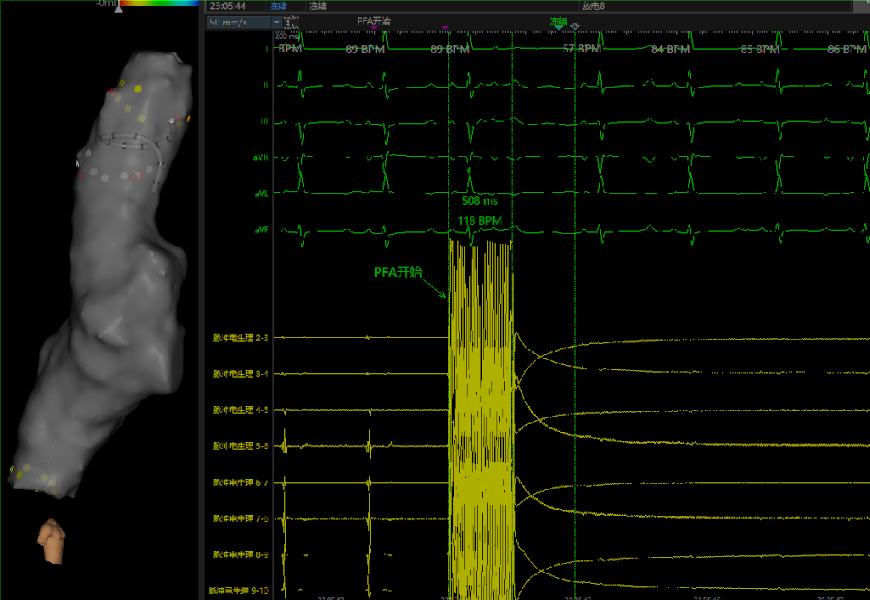

J9九游会电子心脏脉冲电场消融系统动物实验房静脉消融图